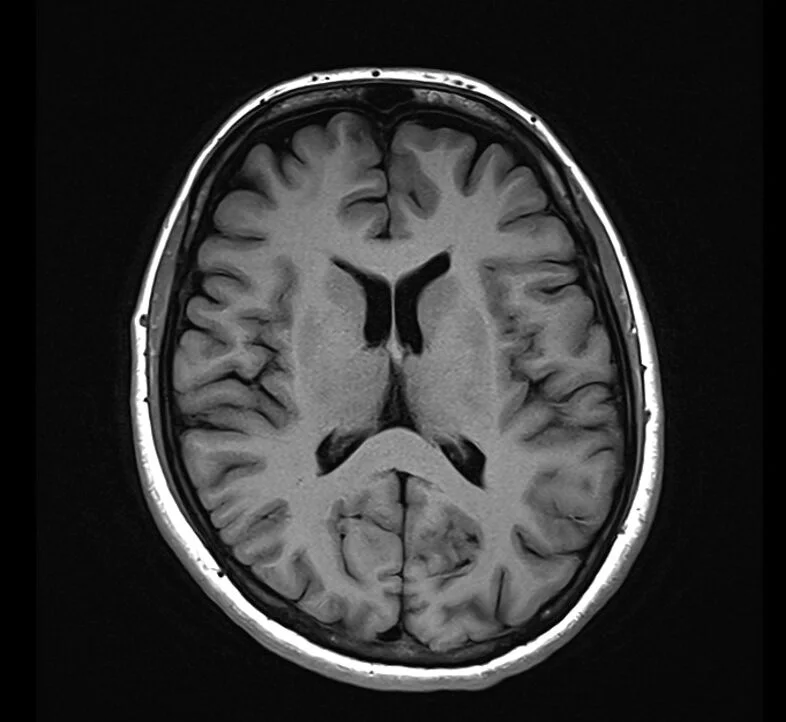

T1 Weighted Imaging

T1 is typically used as an informal anatomy scan.

Fat is Bright (quickly realigns its longitudinal magnetisation with B0)

Water is Dark (has much slower longitudinal magnetisation realignment after an RF pulse and therefore, has less transverse magnetisation)

Applications:

T1 focuses on highlighting anatomy

Useful to detect contrast

As contrast media goes to areas of high blood supply it can detect infections